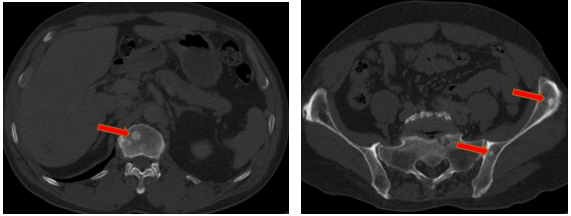

-         Chụp cắt lớp vi tính ổ bụng (08/2025): Nhu mô gan phải có vài nốt, nốt lớn nhất hạ phân thùy VII có nốt giảm tỷ trọng, ngấm thuốc kém sau tiêm đường kính 24mm, hạ phân thùy II, III có nốt 2 giảm tỷ trọng đường kính 13mm và 27mm. Các ổ đặc xương rải rác đốt sống ngực thắt lưng, xương cùng và xương chậu hai bên – theo dõi tổn thương thứ phát

Hình 05: Các ổ đặc xương rải rác đốt sống ngực thắt lưng, xương cùng và xương chậu hai bên – theo dõi tổn thương thứ phát

-         Chụp cắt lớp vi tính ổ bụng (11/2025): Nhu mô gan phải có vài nốt, nốt lớn nhất hạ phân thùy VII có nốt giảm tỷ trọng, ngấm thuốc kém sau tiêm đường kính 8mm, hạ phân thùy II, III có nốt giảm tỷ trọng đường kính (tổn thương giảm đáng kể so với phim chụp ngày 08/2025). Các ổ đặc xương rải rác đốt sống ngực thắt lưng, xương cùng và xương chậu hai bên.

+      Các tổn thương ngấm thuốc kém do di căn tại gan giảm kích thước đáng kể (27mm còn 8mm)